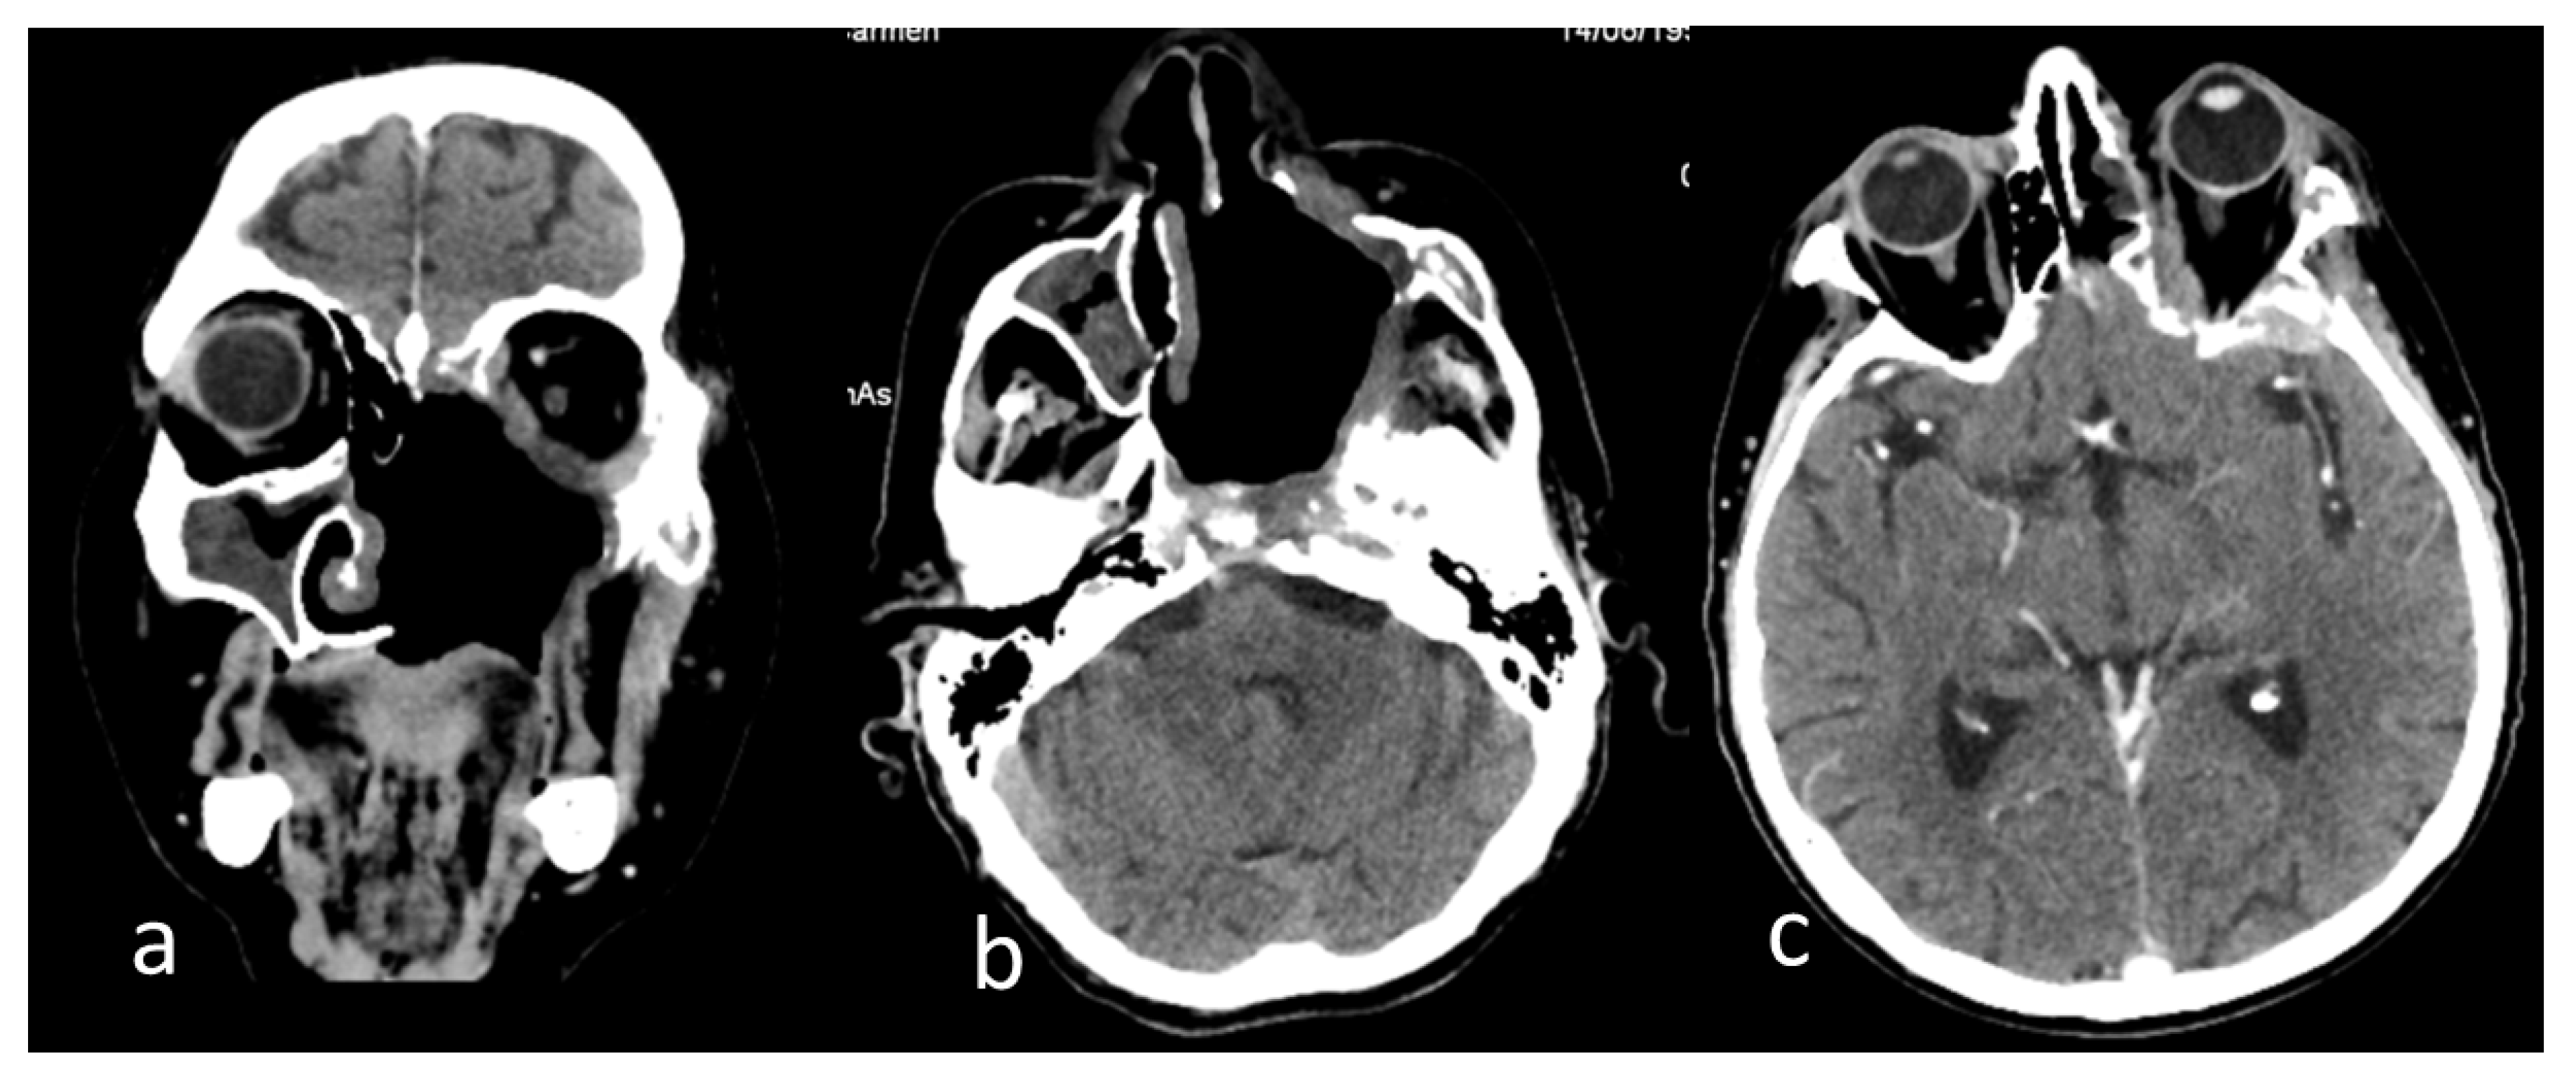

The surgical excisions continued step-by-step, until the complete removal of the necrotic tissues and safe margins was achieved, defined as exclusively healthy and normally vascularized tissues, following oncologic surgery principles. Consequently, the left hemi-palate tissues were lost, leading to a large oro-antral communication that was revealed in a computer tomography examination (Figure 4).

Figure 4.

Computer tomography images of the head after the excision of the left hemi-palate mucormycotic plaque in native examination of the (a) coronal section, (b) axial section, and (c) postcontrast examination axial section. Dysmorphic appearance with bone defects at the maxillary, ethmoidal, sphenoidal, temporal, and zygomatic levels on the left side (a,b); patchy thickening of the mucosa of the right maxillary, ethmoidal sinuses (a,b); fibrotic densification in the left temporal fossa and left exophthalmos (b,c); left temporal thickening and small hypodense area in the neighboring parenchyma (c).